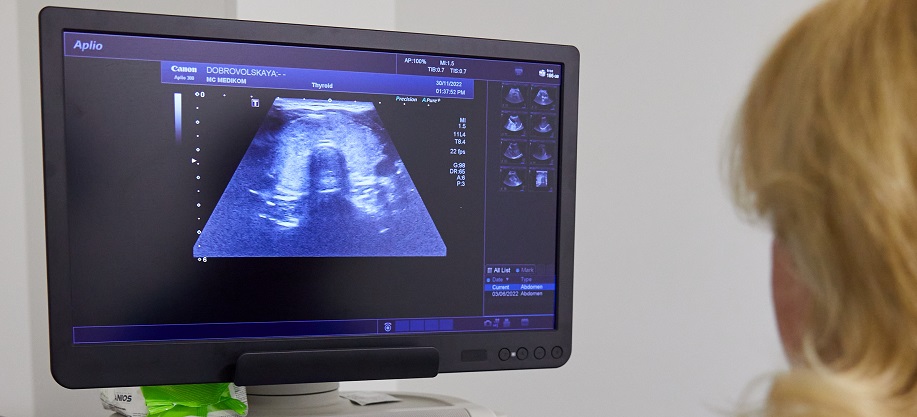

Високоточне УЗД щитоподібної залози можна зробити в клініці МЕДІКОМ. Дослідження проводиться на обладнанні професійними лікарями функціональної діагностики.

Пройти УЗД щитоподібної залози нескладно: тривалість дослідження становить приблизно 20 хвилин. Пацієнта укладають на кушетку на спину із закинутою назад головою. На передню частину шиї наносять гель, що сприяє проходженню ультразвуку. Обстеження органу проводять датчиком, що сканує тканини залози. Результат дослідження виводиться на дисплей у режимі реального часу. Процедура не спричиняє болючих відчуттів, можливий невеликий дискомфорт через незручне положення голови.

- Наші лікарі використовують найсучасніше обладнання для проведення УЗД-діагностики. Професіоналізм фахівців клініки унеможливлює будь-які помилки.